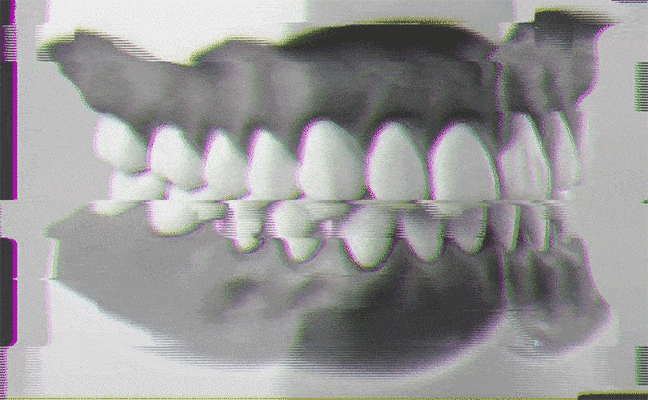

La ansiedad y el estrés tienen multitud de expresiones en el organismo. A veces, incluso achacamos a estos estados de ánimo dolencias que nada tienen que ver con ellos. (Sí, a veces esa caída del pelo no se debe a «los nervios», sino, por ejemplo, a una anemia sin diagnosticar). Pero donde sin duda dejan una huella inequívoca es en la boca. El incremento de la tensión emocional nos lleva, en muchas ocasiones, a apretar la mandíbula, y hasta a rechinar los dientes, de forma totalmente inconsciente e involuntaria. Y puede suceder tanto de día, mientras realizamos concentrados cualquier tarea, como de noche cuando dormimos. Una de las consecuencias de esta patología, denominada en medicina como 'bruxismo', es un desgaste tal de las piezas dentales que incluso puede llegar a quebrarse.

Este trastorno se caracteriza por la alteración de los músculos mandibulares y de las estructuras adyacentes. De hecho, uno de los primeros síntomas es sentir molestias en la mandíbula y notar chasquidos al abrir y cerrar la boca. Junto a ello, hay que estar alerta ante la presencia de dolores cabeza y de cuello, derivados de la tensión muscular que provoca el 'apretar de dientes', dicho coloquialmente. Por último, observar si hay desgaste en los dientes o en el esmalte.

Para ello, ante los primeros síntomas ya descritos, desde el Colegio de Odontología se recomienda pasar por un especialista para realizar una valoración completa antes de autodiagnosticarse. «Esto incluye una historia clínica con preguntas sobre salud dental general, medicación actual y hábitos de sueño, entre otros campos de interés. Debe complementarse con una exploración bucodental, buscando signos de desgaste, así como la posible presencia de dolor en la musculatura mandibular o ruidos en la articulación. Este estudio muchas veces se complementa con una toma de impresiones, análisis de los modelos y radiografías», detalla el citado especialista.